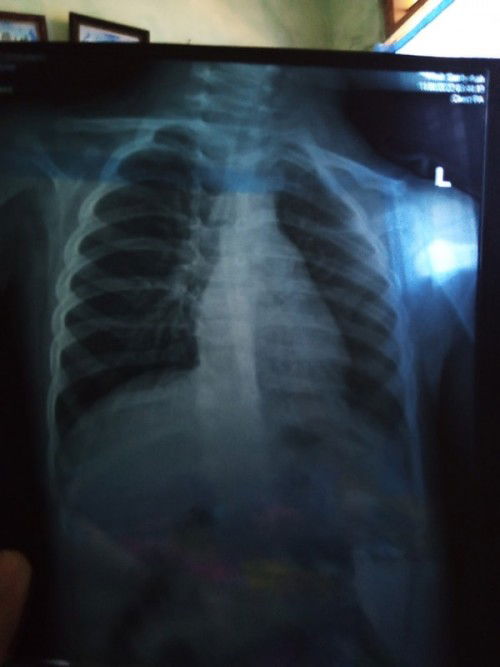

bronkopneumonia

Bund ada anaknya yg sakit bronkopneumonia? Qadaraallah anak saya bulan lalu kena dan sudah berobat, saya mau tanya bund apakah bronkopneumonia bisa sembuh total? #seriusnanya #bantusharing